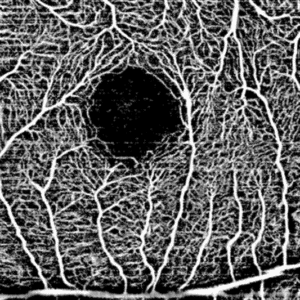

Modulo de Angiografía

Tomógrafo de coherencia óptica HOCT-1F 80k